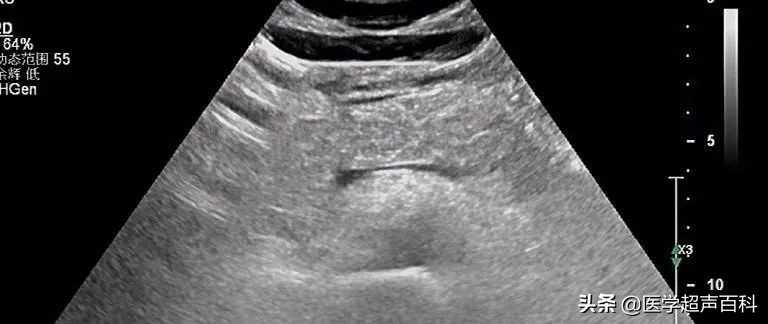

水肿型胰腺炎:胰腺稍大, 边缘规整,胰头、体部回声减低,分布前均质